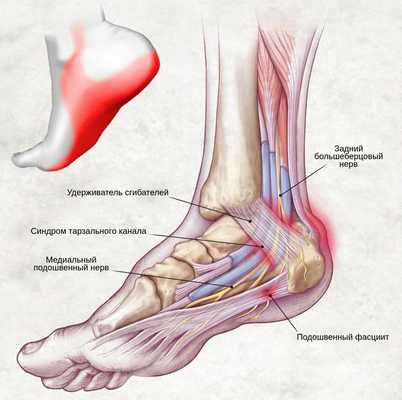

Синдром тарзального канала

Синдром тарзального канала (СТК), либо, как еще называют данный недуг - туннельный синдром предплюсны, представляет собой заболевание, сопровождаемое дискомфортными и болевыми ощущениями, спровоцированными чрезмерным сдавливанием и натяжением расположенного в канале предплюсны большеберцового нерва.

Проходящий по поверхностям таранной и пяточной костей (в задней части лодыжки), канал предплюсны ограничивается удерживателем сухожилий-сгибателей. Постоянное раздражение находящегося в канале нерва вызывает стопное онемение и, соответственно, боль в данной области.

С точки зрения анатомии, канал предплюсны представляет собой пространство, где размещены сухожилия сгибателей пальцев (в том числе и первого), а также большеберцовые нерв и артерия. В свою очередь, большеберцовый нерв подразделяется на латеральный, пяточный и медиальный нервы.

Рис 1. Анатомические особенности канала предплюсны.